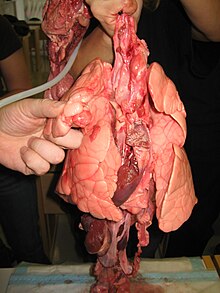

Le poumon est un organe intrathoracique pair de l'appareil respiratoire, permettant l'échange des gaz vitaux, notamment l'oxygène et le dioxyde de carbone. L'oxygène est nécessaire au métabolisme de l'organisme, et le dioxyde de carbone doit être évacué. Cet organe serait apparu sur des espèces marines il y a au moins 420 millions d’années. Chez l'humain, le poumon droit pèse environ 650 grammes tandis que le poumon gauche pèse 550 grammes environ[1].

L'être humain possède deux poumons (un gauche et un droit), situés à l'intérieur du thorax dans les cavités pleurales, et séparés l'un de l'autre par le médiastin. Au travers de la plèvre, les poumons sont en contact, en leur face inférieure, avec le diaphragme, sur leurs faces antérieures, latérales et postérieures, avec la cage thoracique. Le sommet du poumon affleure le creux sus-claviculaire, à la base du cou.